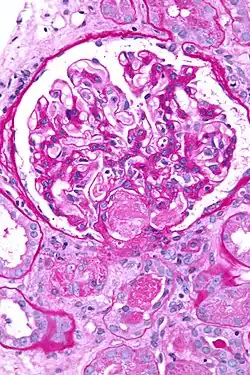

| Micrograph showing acute thrombotic microangiopathy due to DIC in a kidney biopsy. A clot is present in the hilum of the glomerulus (center of image). | |